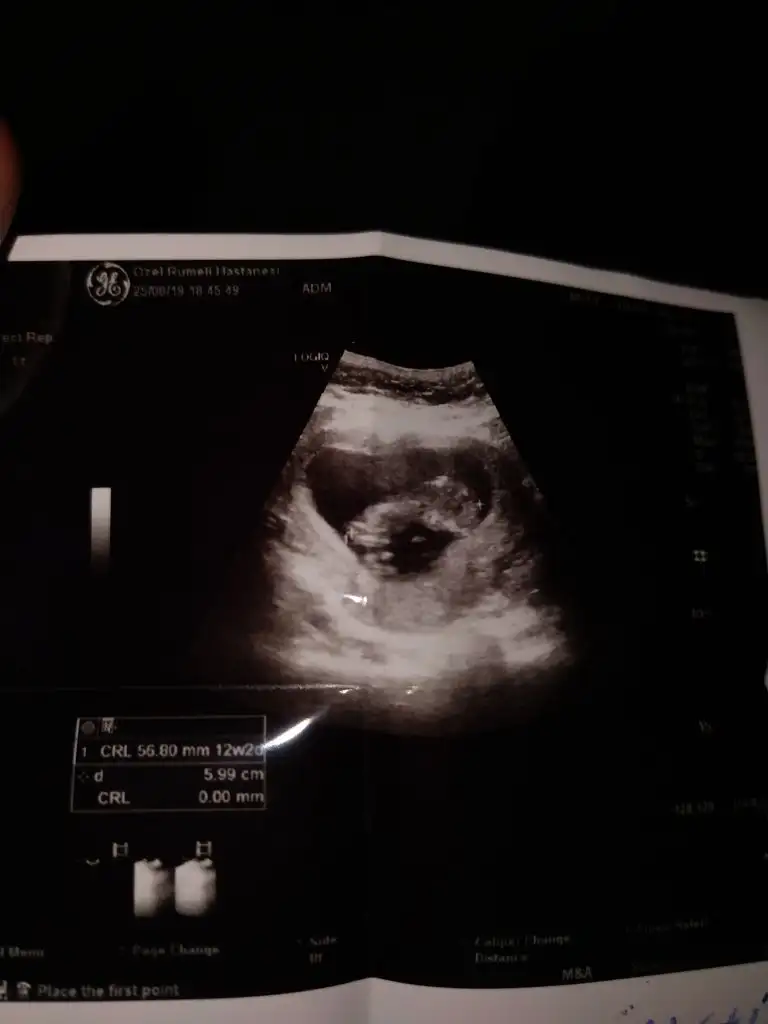

ErkekEki Görüntüle 2301494 Eki Görüntüle 2301495 Merhaba bende tahmin alabilirmiyim

ErkekSelam kızlar. 10+5 günlük hamileyim, var mı bi tahminleriniz

Net olmamakla birlikte kız başka usg varsa paylaşın

Bunda hic belli değil bence ama birde bu var :) yinede tesekkur ederimNet olmamakla birlikte kız başka usg varsa paylaşın

KızBunda hic belli değil bence ama birde bu var :) yinede tesekkur ederim